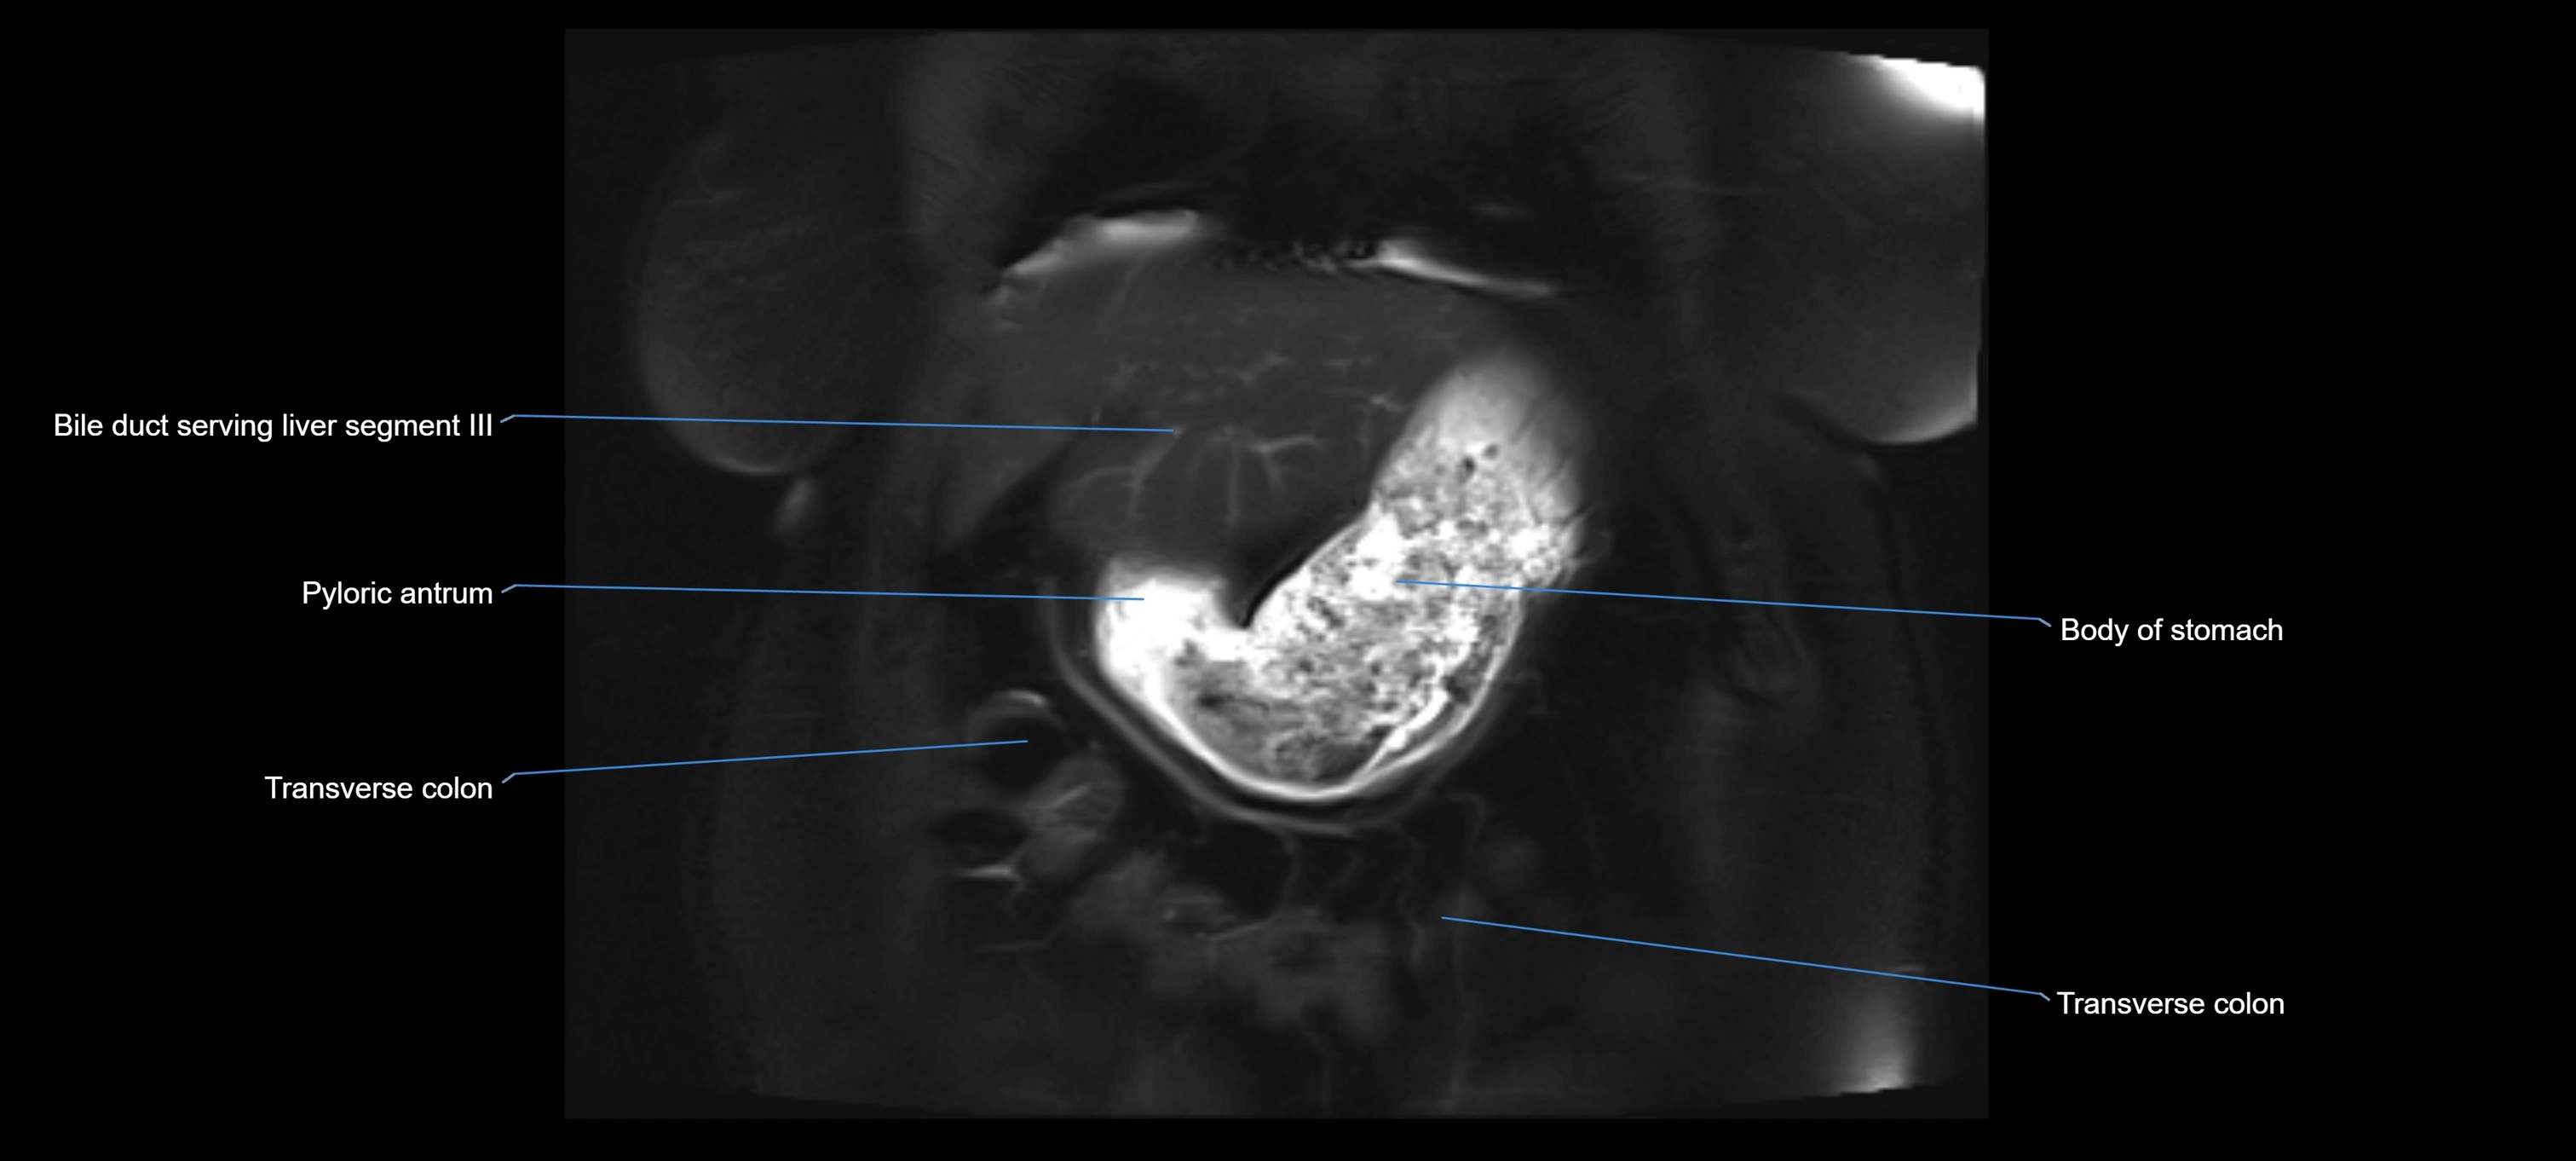

MRI image

image